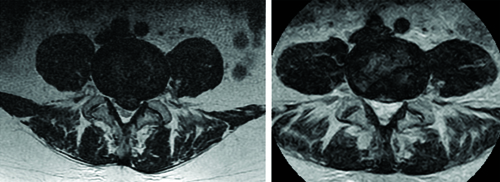

To provide a comprehensive understanding of the changes attained during the treatment program, MRI images of patient one are depicted in both [Table/Fig-6,7]. The improvement achieved is evident from both sagittal and transverse plane images. However, for the sake of quantitative evaluation, only the transverse images were processed. The obtained quantitative data are illustrated through box plot graphs in [Table/Fig-8]. These graphs depict the changes resulting from the treatment, showing a decrease in the AP length and area of the herniation, alongside an increase in the canal indicators. Of particular significance is the observed change in the HI parameter, which provides a comprehensive assessment of the achieved improvements.

An illustration demonstrating the comparison between a transverse T2-weighted MRI image obtained during the initial visit (on the left) and one acquired after the completion of the treatment program (on the right).